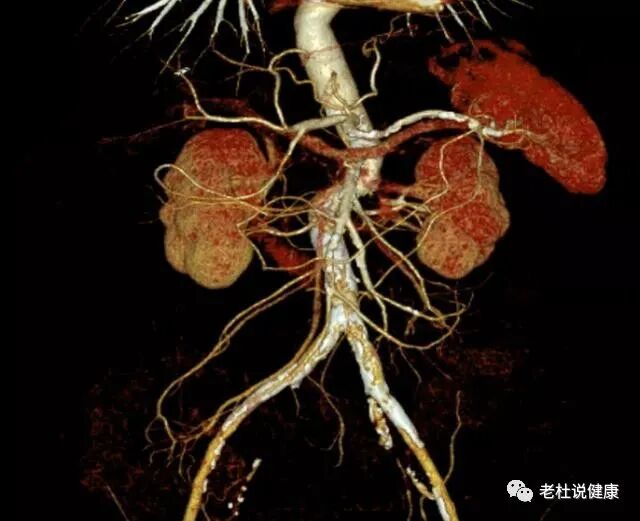

接诊医生安排做了腹部平扫CT、和腹部血管成像检查,结果发现老太太的结肠肝区肠壁明显增厚,周围渗出性改变,腹部多处血管严重狭窄;

腹部多处血管严重狭窄